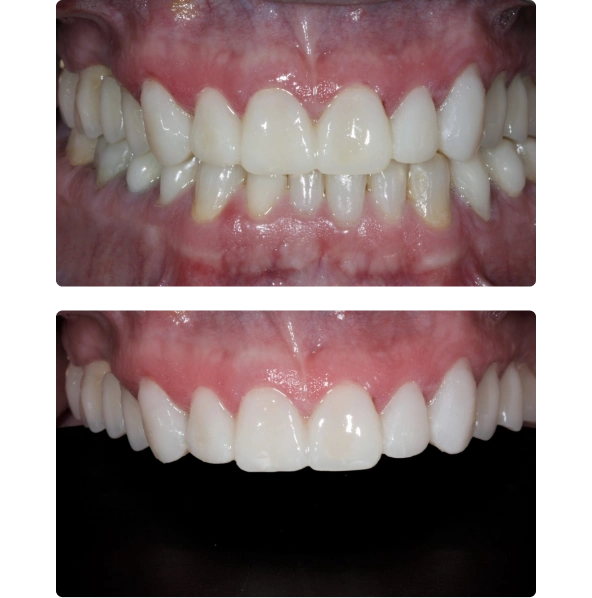

Antes

Depois

Sua queixa principal era a de que tinha feito um tratamento ortodôntico de mais ou menos dois anos de duração, mas continuava insatisfeito com a função mastigatória e a estética de seus dentes.

Foram confeccionadas facetas cerâmicas de dentes caninos a caninos superiores e inferiores, ponte fixa na região superior direita e coroas unitárias em dissilicato de lítio nos pré molares e molares.